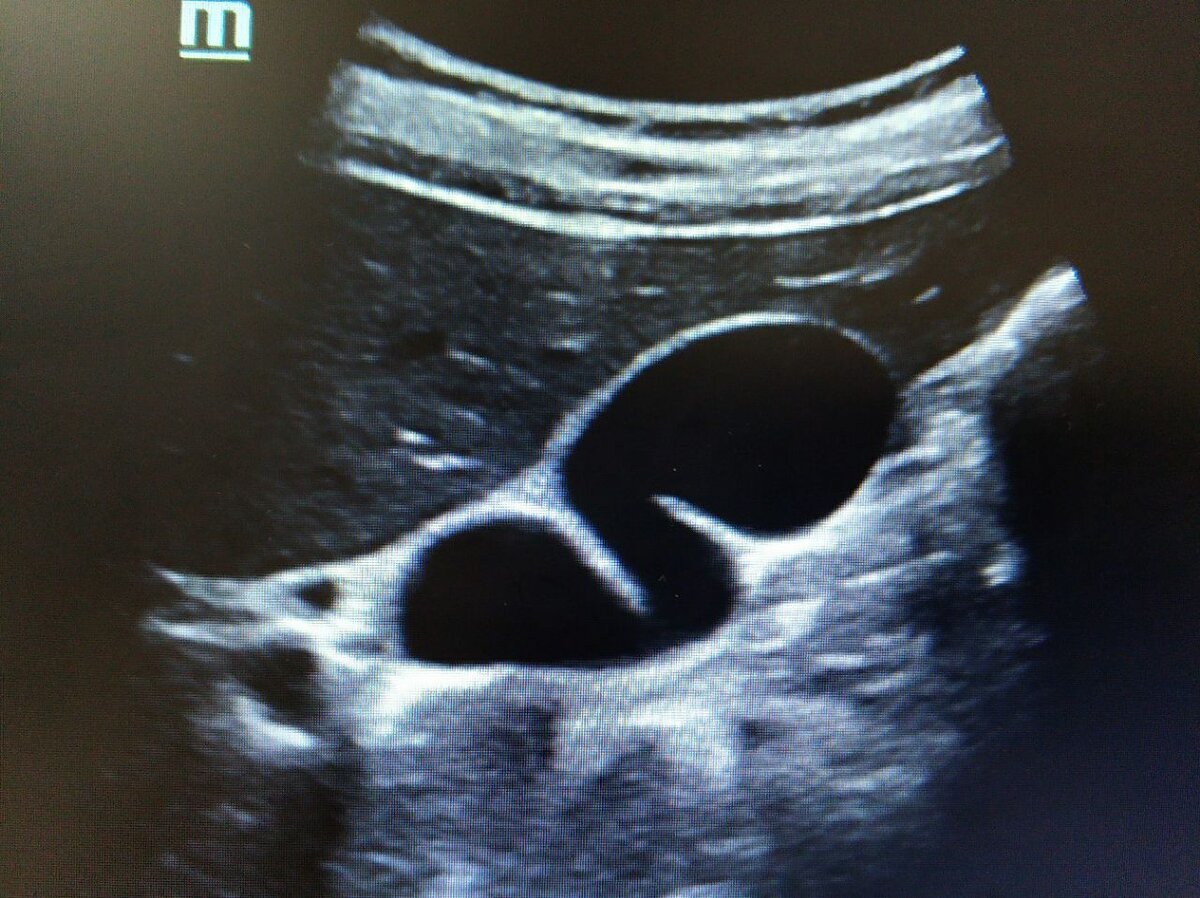

Деформация желчного пузыря

Желчный пузырь как произведение искусства. Извитой вид пузыря, вызванный перегородками, часто водит докторов за нос весьма извилистыми путями. Он символизирует целую череду распростаренных заблуждений связи дискинезии и формы. Когда-то давно, перегородок пузыря находили меньше. С ростом технологий их стало гораздо больше, каждый второй пациент их имеет. Это абсолютная норма, вариантная анатомия, которая никак не связана с функцией желчного пузыря. #УЗД #УЗИ #sonography #ultrasound #желчный